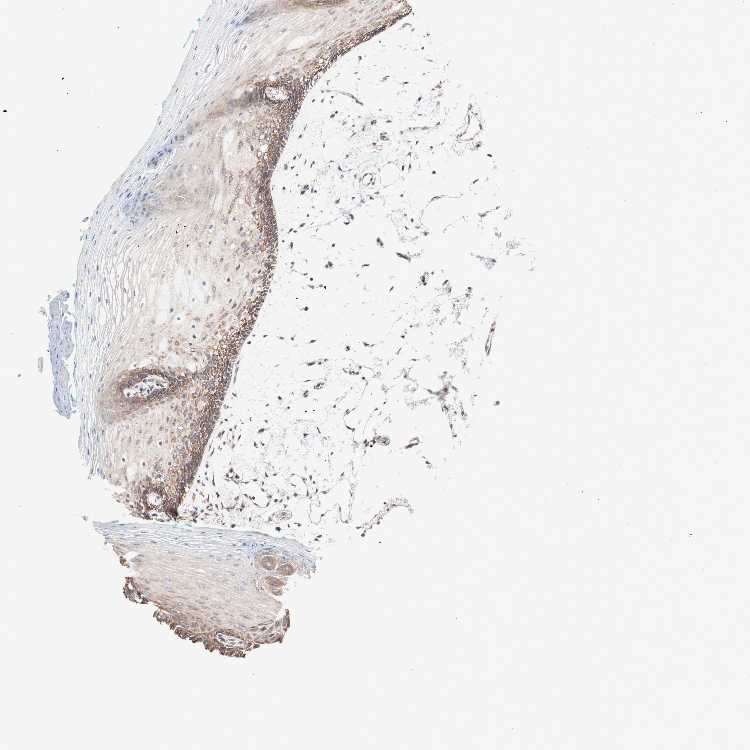

TISSUE PRIMARY DATA ORAL MUCOSA Show tissue menu

ORAL MUCOSA - Antibody stainingi

Antibody staining in the annotated cell types in the current human tissue is reported as not detected, low, medium, or high, based on conventional immunohistochemistry profiling in selected tissues. This score is based on the combination of the staining intensity and fraction of stained cells.

Each image is clickable and will lead to virtual microscopy that enables deeper exploration of all samples and also displays staining intensity scores, fraction scores and subcellular localization as well as patient and tissue information for each sample.

Antibody HPA010773

Squamous epithelial cells Medium